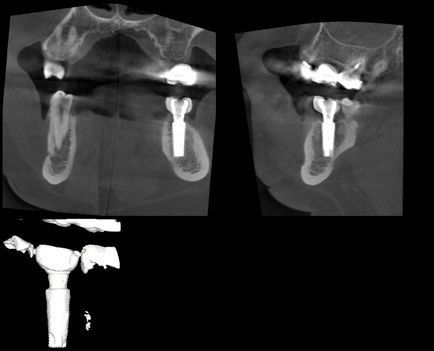

És végül, az áttörés a fogászatban, CT váltak elérhetővé használatra klinikákon. A kép a számítógép, láthatjuk 3D voxel, ezek izotropichny, ami objektumokat a kép pontosan lemérjük minden irányban, hogy szimulálják a további kezelési terv CBCT lehet különböző szögekből nézve. Ezért ez a fajta vizsgálat használjuk, mint a sebész beültetésre, és az orvosok, hogy tanulmányozza a topográfia a fogak gyökereit és a csatornák, valamint ezek mennyiségét. A parodontológia szakemberek tanulmányozzák az összeg csontszövet is tervez egy művelet visszaállítani. Az alábbiakban példák használata CBCT a diagnózis és a kezelés különböző területein fogászat.

Hely az implantátum a csontba